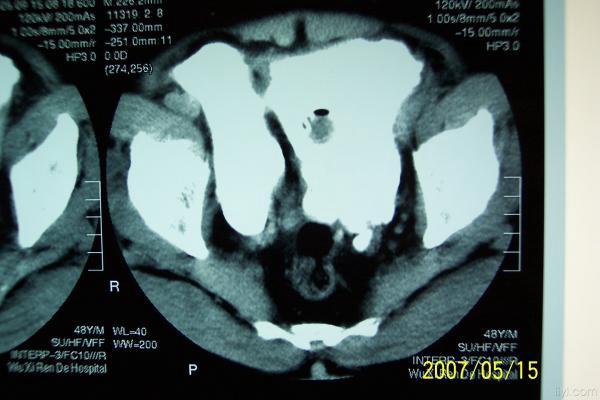

分享下一例巨大膀胱憩室的图片

分享下一例罕见病历的图片,这是我遇到的最大巨大膀胱憩室。

双膀胱,少见,要看输尿管注入膀胱的位置。

考虑双膀胱的可能性大.

双膀胱畸形